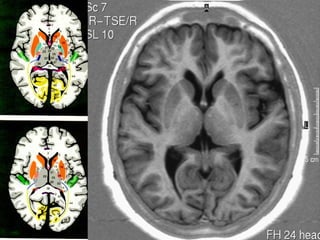

GÂNGLIOS DA BASE

NÚCLEO

CAUDADO

cabeça

corpo

LENTIFORMES

putamen

Globo pálido

Anatomia cerebral

Diencéfalo

• Epitálamo ( núcleos e comissura habenulares ,

pineal e comissura posterior ).

• Tálamo ( 80 % do diencéfalo ),

•   Hipotálamo ,

•   Subtálamo

Tálamo

• Massas nucleares , grandes e dispostas

de forma simétrica.

• Substância cinzenta , mede 3,0 x 1,5 cm ,

• Aglomerações de neurônios e núcleos,

• Forma a parede lateral do III ventrículo.

• Limite anterior    tubérculo

anterior,

• Limite posterior    núcleo pulvinar ,

• Limite superior     estria medular,

• Limite inferior    região tegmal sub talâmica.

HIPOTÁLAMO

TRATO

ÓPTICO

CORPOS

MAMILARES